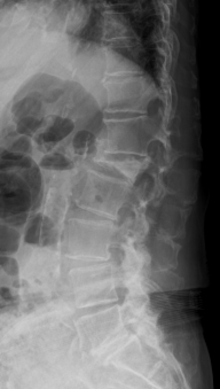

第11胸椎椎体骨折を認めます。骨折部には黒いギャップが存在し、偽関節を呈しています。軽微な後壁損傷も認めます。第1腰椎は椎体骨折後の楔状化変形を認めますが、癒合しています。

骨折部にステントの殻を挿入し、ステント内に骨セメントを充填して治療しました。背中に5mm程度の切開を2か所おいて施します。ステントにより再圧潰が防がれ、また隣接椎体に対する負担も軽減されることが報告されています。